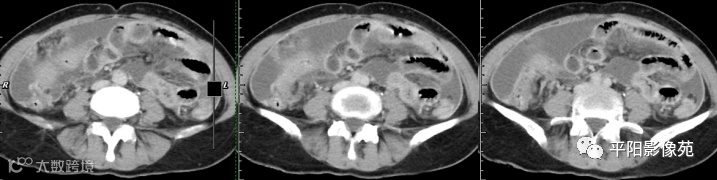

腹部增强 动脉期

腹部增强 门脉期

腹部增强 延迟期

壁腹膜增厚伴或不伴腹水;增厚的腹膜光滑、均匀,呈线带状,部分可见腹膜结节,网膜及肠系膜广泛浸润性改变;增强扫描明显强化。

合并淋巴结肿大,可钙化,若中心干酪样坏死,增强扫描环形强化

湿型:渗出性高密度腹水(CT值20-45HU),高密度由于高蛋白和细胞含量多可能。